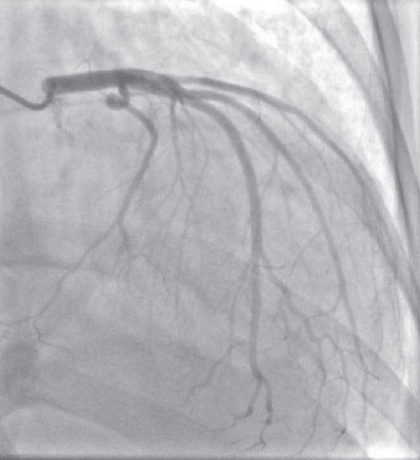

为明确有无缺血性左心室衰竭,行冠脉造影检查,未见明显异常。

图3 冠脉造影结果